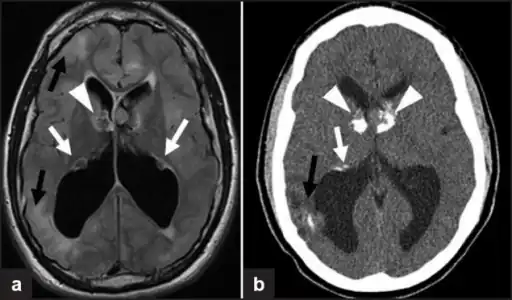

- a,b)Images of subependymal giant cell astrocytomas arrowheads

- MRI of brain with sub-ependymal giant cell astrocytoma

Diagnosis is made by imaging with a contrast-enhanced MRI or CT scan of the brain.[3]